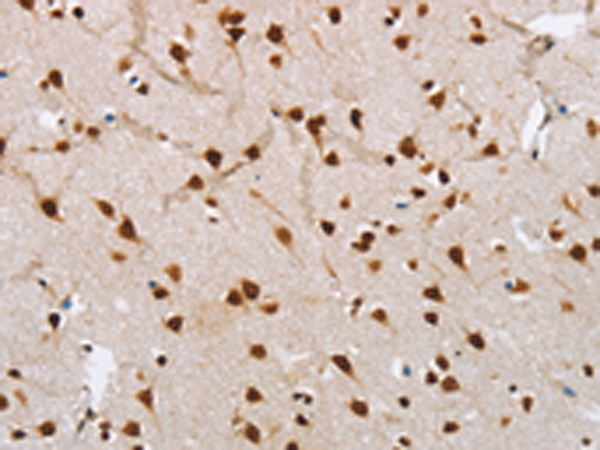

分类: 科研抗体货号: P11579别名: ADNP1应用: IHC反应种属: Human, Mouse, Rat